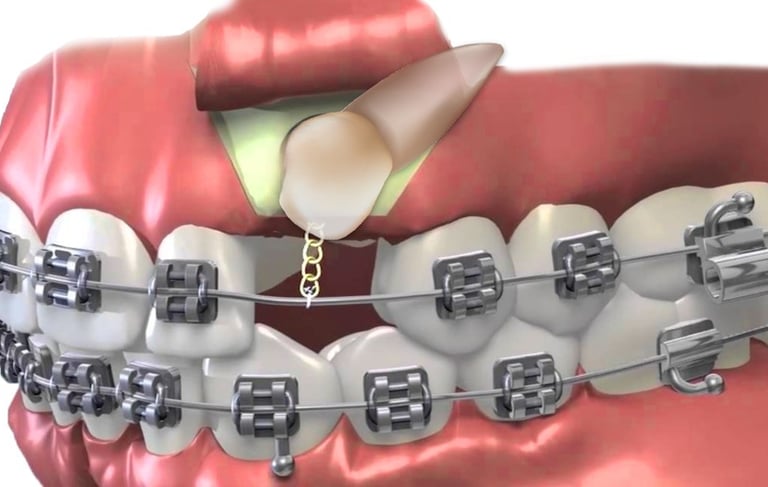

La fenestración en cirugía maxilofacial es un procedimiento quirúrgico que se utiliza para exponer una parte del hueso o un diente que está retenido o impactado dentro de la encía o el hueso. Este procedimiento es común en el tratamiento de dientes que no han erupcionado, como los caninos superiores, o para manejar dientes retenidos.

Fenestración